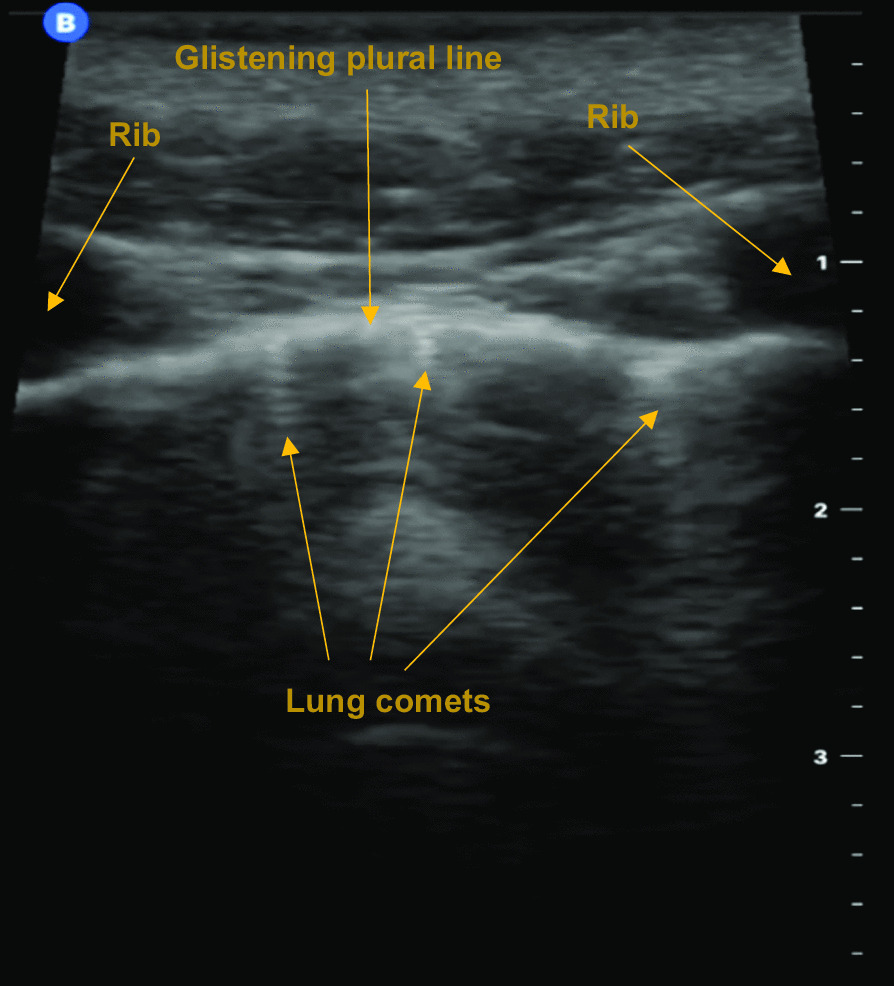

Background: Auscultating for breath sounds to assess for pneumothorax in the helicopter emergency medical services (HEMS) settings can be extremely challenging. Thoracic point of care ultrasound (POCUS) offers a seemingly more useful visual (rather than audible) alternative. This review critically and quantitatively evaluates the use of thoracic POCUS for pneumothorax in the HEMS setting.

Results: Twelve studies reporting on n = 1,936 images from medical and trauma patients were included in qualitative synthesis. Studies were nearly all observational designs. Most images were acquired by nurses or paramedics who were previously novices to ultrasound. The reference standard was predominantly CT. Specificity results were unanimously precise and very high, whereas sensitivity results were imprecise and extremely variable. Meta-analysis of eight studies involving n = 1,713 images yielded pooled sensitivity 61% (95% CI: 27-87%; I2 = 94%) and pooled specificity 99% (95% CI: 98-100%; I2 = 89%). Six studies involving n = 315 images reported practicality. The highest or second highest categorisation of image quality was reported in around half of those images.

Conclusion: Thoracic POCUS is highly specific but has extremely variable sensitivity for pneumothorax when performed in the HEMS setting. This is from purely a diagnostic (not clinical) perspective. Sensitivity increases when only clinically significant pneumothoraces are considered. Case reports reveal thoracic POCUS can appropriately alter treatment and triage decisions, but only for a small number of patients. It appears predominantly useful in mitigating against unnecessary interventions. More research reporting patient focused outcomes is required. In the meantime, thoracic POCUS appears to offer a more appropriate visual alternative to auscultation for breath sounds when assessing for pneumothorax in the HEMS setting.